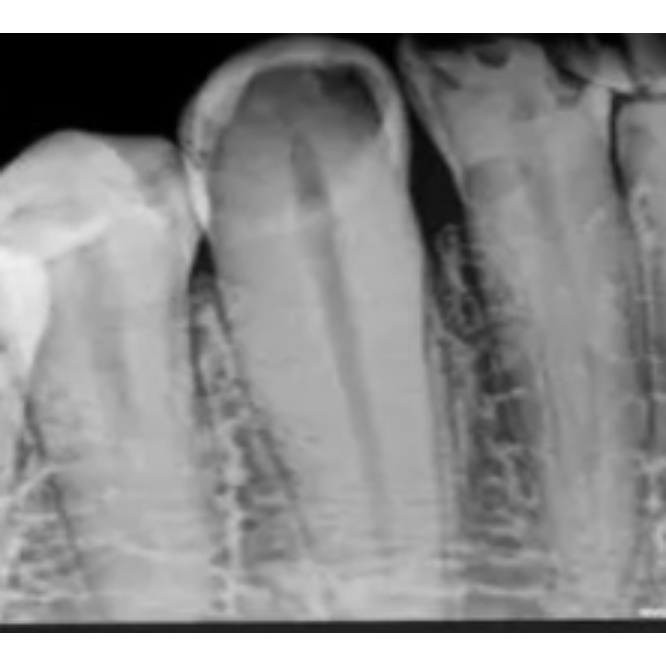

Single tooth IOPA

Single tooth IOPA scan is available C-8/193 sector - 8 Rohini delhi 9811552279, 7827070020 A single tooth IOPA (Intraoral Periapical Radiograph) is a dental X-ray that captures a detailed image of one specific tooth and the surrounding bone and tissue, including the tooth's root and the periodontal ligament. This diagnostic tool is used by dentists to identify issues like tooth decay, abscesses, bone loss, or root fractures that may not be visible on the surface of the tooth. Purpose of a Single Tooth IOPA Detecting Decay and Disease: IOPAs can reveal cavities, tooth decay, and other dental problems that are hidden from view. Assessing Root and Bone Health: The X-ray provides a clear view of the tooth's root structure and the bone supporting it, which is essential for diagnosing infections, cysts, and bone loss. Monitoring Treatment Progress: Dentists use IOPAs to monitor the success of treatments, such as root canals, dental implants, and other restorative procedures. Evaluating Tooth Anomalies: It helps in identifying developmental issues or anomalies in the tooth's structure, like a dens invaginatus. Identifying Abscesses and Cysts: A single tooth IOPA can show the presence of abscesses or cysts around the tooth's root. How it Works A small film or digital sensor is placed inside the patient's mouth next to the tooth to be examined. An X-ray beam is directed at the tooth and sensor to create a detailed image of the tooth's entire length, from the crown to the root tip, and the surrounding areas. The image is then developed to reveal the internal structures of the tooth and bone, allowing the dentist to make an accurate diagnosis and treatment plan.